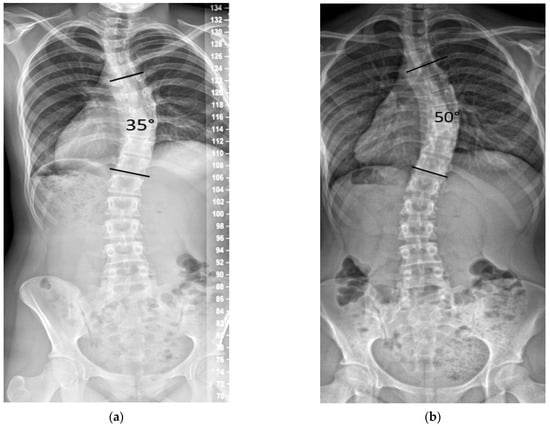

The unclear understanding of the etiology of idiopathic scoliosis (IS) is the main reason for study of this deformity within the wider scope of its management. This management includes prevention, including school scoliosis screening, non-surgical treatment in the form of physiotherapeutic specific scoliosis exercises (PSSEs), bracing or a combination of these two, and finally surgical treatment. All these areas of study are relevant to this Special Issue, and any progress experienced within the above areas is useful for individuals with scoliosis. The quality of life of children and adolescents with IS has recently resulted in a number of publications based on its management. Due to the advancements mentioned above, it is expected that new articles based on the most sophisticated types of treatment will be submitted, as well as new relevant questionnaires to assess the QoL.In all publications, IS is described as a three-dimensional deformity. In reality, it is four-dimensional if the survival time parameter is considered, as individuals with the deformity will have the deformity until death. The importance of this comment is particularly pertinent in operated patients, as this group—treated with the current very powerful posterior spinal fusion systems—show a significant percentage of the so called “adjacent level disease” in long term follow-up, often leading to a revision of these operations. Furthermore, the reported complications, using any other modern surgical technique, may encourage the study of IS etiology of so that the treatment will eventually be etiological rather than symptomatic as it is today, minimizing complications, procedures, hospitalizations, and the burden on families.